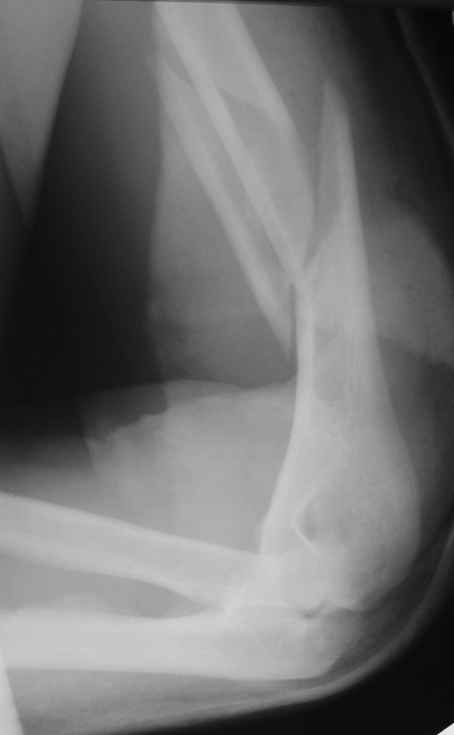

Снимки до, через 1 и 2 мес. после синтеза.

Теперь непосредственно по больному. Лечим функциональной повязкой, добились вот чего (приложение). Будем признательны за дальнейший комментарий - мое мнение, что можно продолжить без операции.